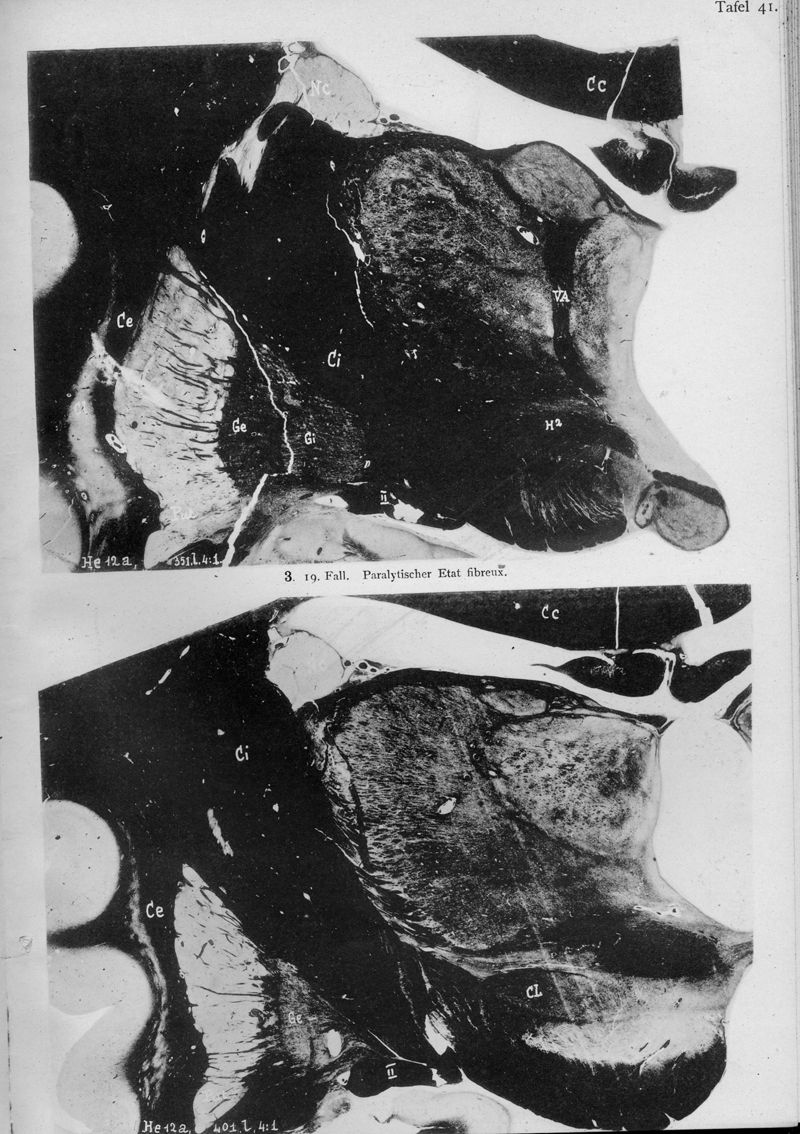

VOGT, Cécile / VOGT, O.

In : Journal für Psychologie und Neurologie,

1920, Vol. 25, pp. 627-846